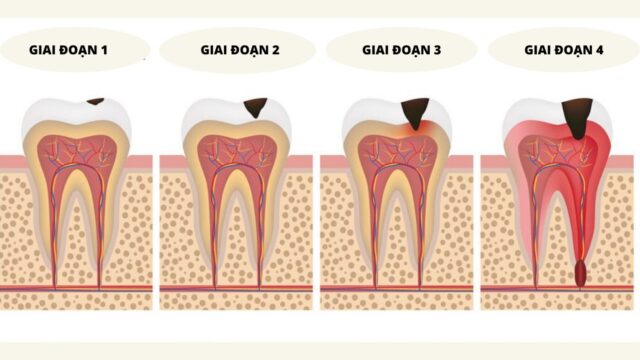

Trong giai đoạn đầu, viêm quanh răng thường bắt nguồn từ mảng bám và cao răng tích tụ lâu ngày, gây kích thích và viêm nhiễm tại các tổ chức liên quan. Bệnh lý này bắt đầu bằng viêm lợi, sau đó lan rộng ra các dây chằng quanh răng và xương ổ răng, làm suy yếu cấu trúc nâng đỡ của răng.

Khi bệnh tiến triển, các mô liên kết bị phá hủy, dẫn đến tụt lợi, răng dễ lung lay hoặc thậm chí mất răng. Điều đáng lo ngại là quá trình này diễn ra âm thầm, ít có triệu chứng rõ ràng ban đầu, khiến nhiều người chủ quan bỏ qua việc chăm sóc cần thiết.